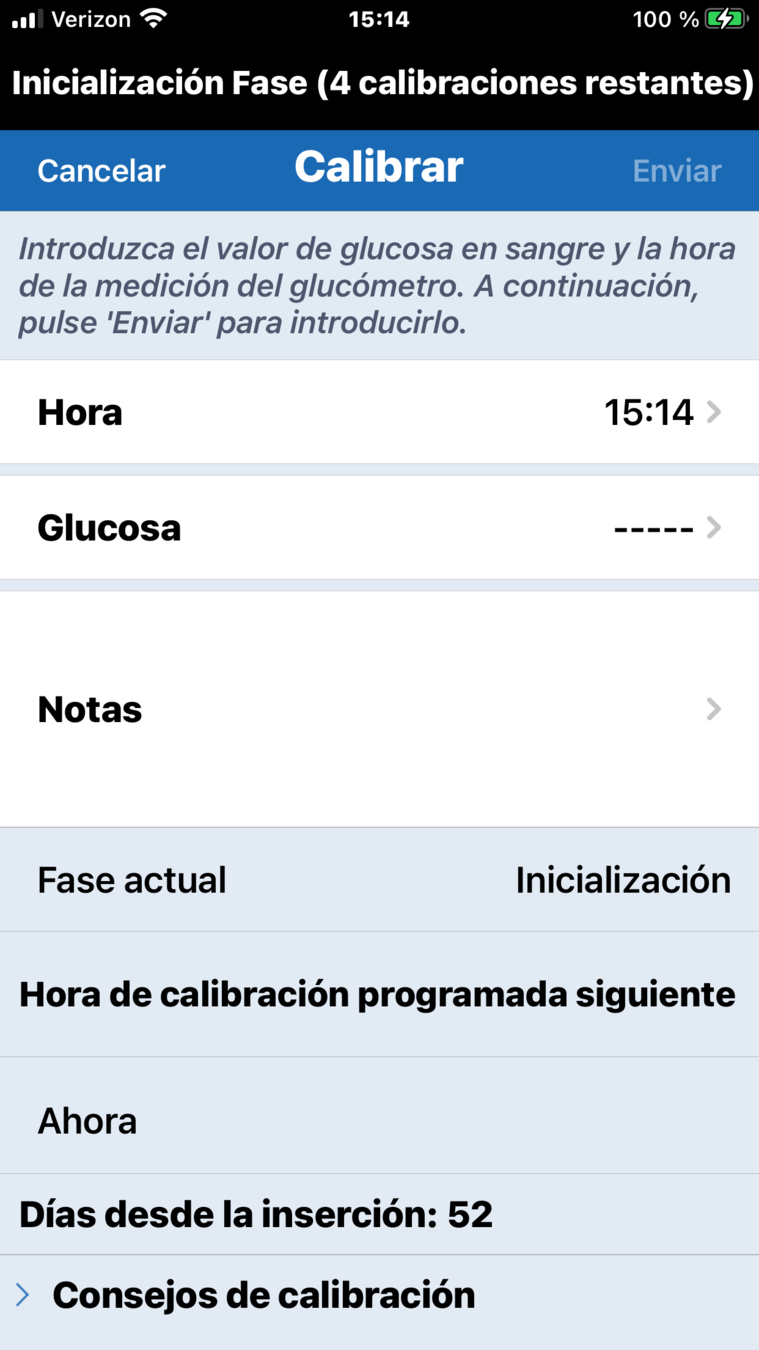

Para introducir una calibración, haga una comprobación de glucosa en sangre mediante punción capilar…

… y toque en el botón Calibrar.

Toque Glucosa…

… y desplácese para introducir el valor correcto de glucosa en sangre.

A continuación, toque OK.